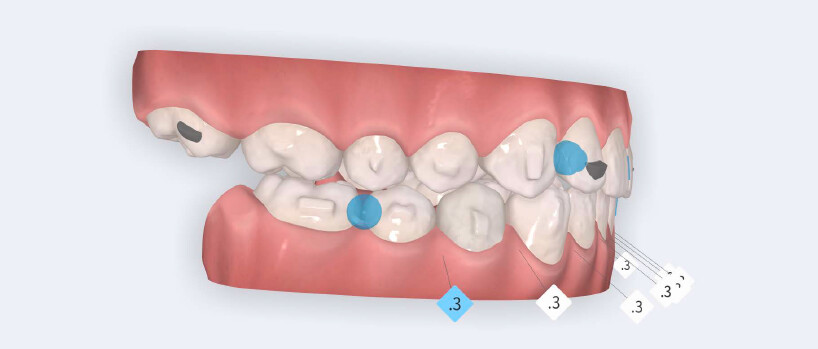

The treatment followed the Angel Aligner A6 mandibular advancement protocol, with the primary objective of achieving early correction of the sagittal discrepancy while simultaneously addressing dental alignment and transverse coordination.

• Initiation of mandibular advancement from the 4th aligner using mandibular advancement blocks;

• Arch expansion to resolve crowding and improve transverse coordination;

• Selective interproximal reduction in the mandibular anterior region to create space and control incisor inclination;

• Programmed intrusion of the maxillary central incisors to reduce the gingival display and correct the gummy smile;

• Intrusion of mandibular incisors and canines to level the Curve of Spee;

• Use of Class II elastics on Angel Buttons during the refinement phase to reinforce sagittal mechanics, introduced during the additional aligners stage.

The treatment was carried out using Angel Aligner clear aligners, with strict adherence to periodontal biological limits. Both maxillary incisor intrusion and transverse expansion were carefully monitored throughout the process to prevent any periodontal compromise. Mandibular advancement was initiated directly from the 4th aligner using advancement blocks, eliminating the need for a preliminary pre-advancement phase. The patient was at the CS3 stage of cervical vertebral maturation, corresponding to the pubertal growth spurt, a biologically favorable period for condylar remodeling and skeletal adaptation. A total of 35 aligners with advancement blocks were used, followed by 10 additional aligners incorporating Class II elastics on Angel Buttons to finalize rotations and alignment. With weekly aligner changes, the overall treatment duration was approximately 45 weeks (10 months), aligning with the expected biological timeline for condylar remodeling. For mandibular anterior intrusion, the Frog Protocol combined with interproximal reduction (IPR) achieved complete leveling of the Curve of Spee.